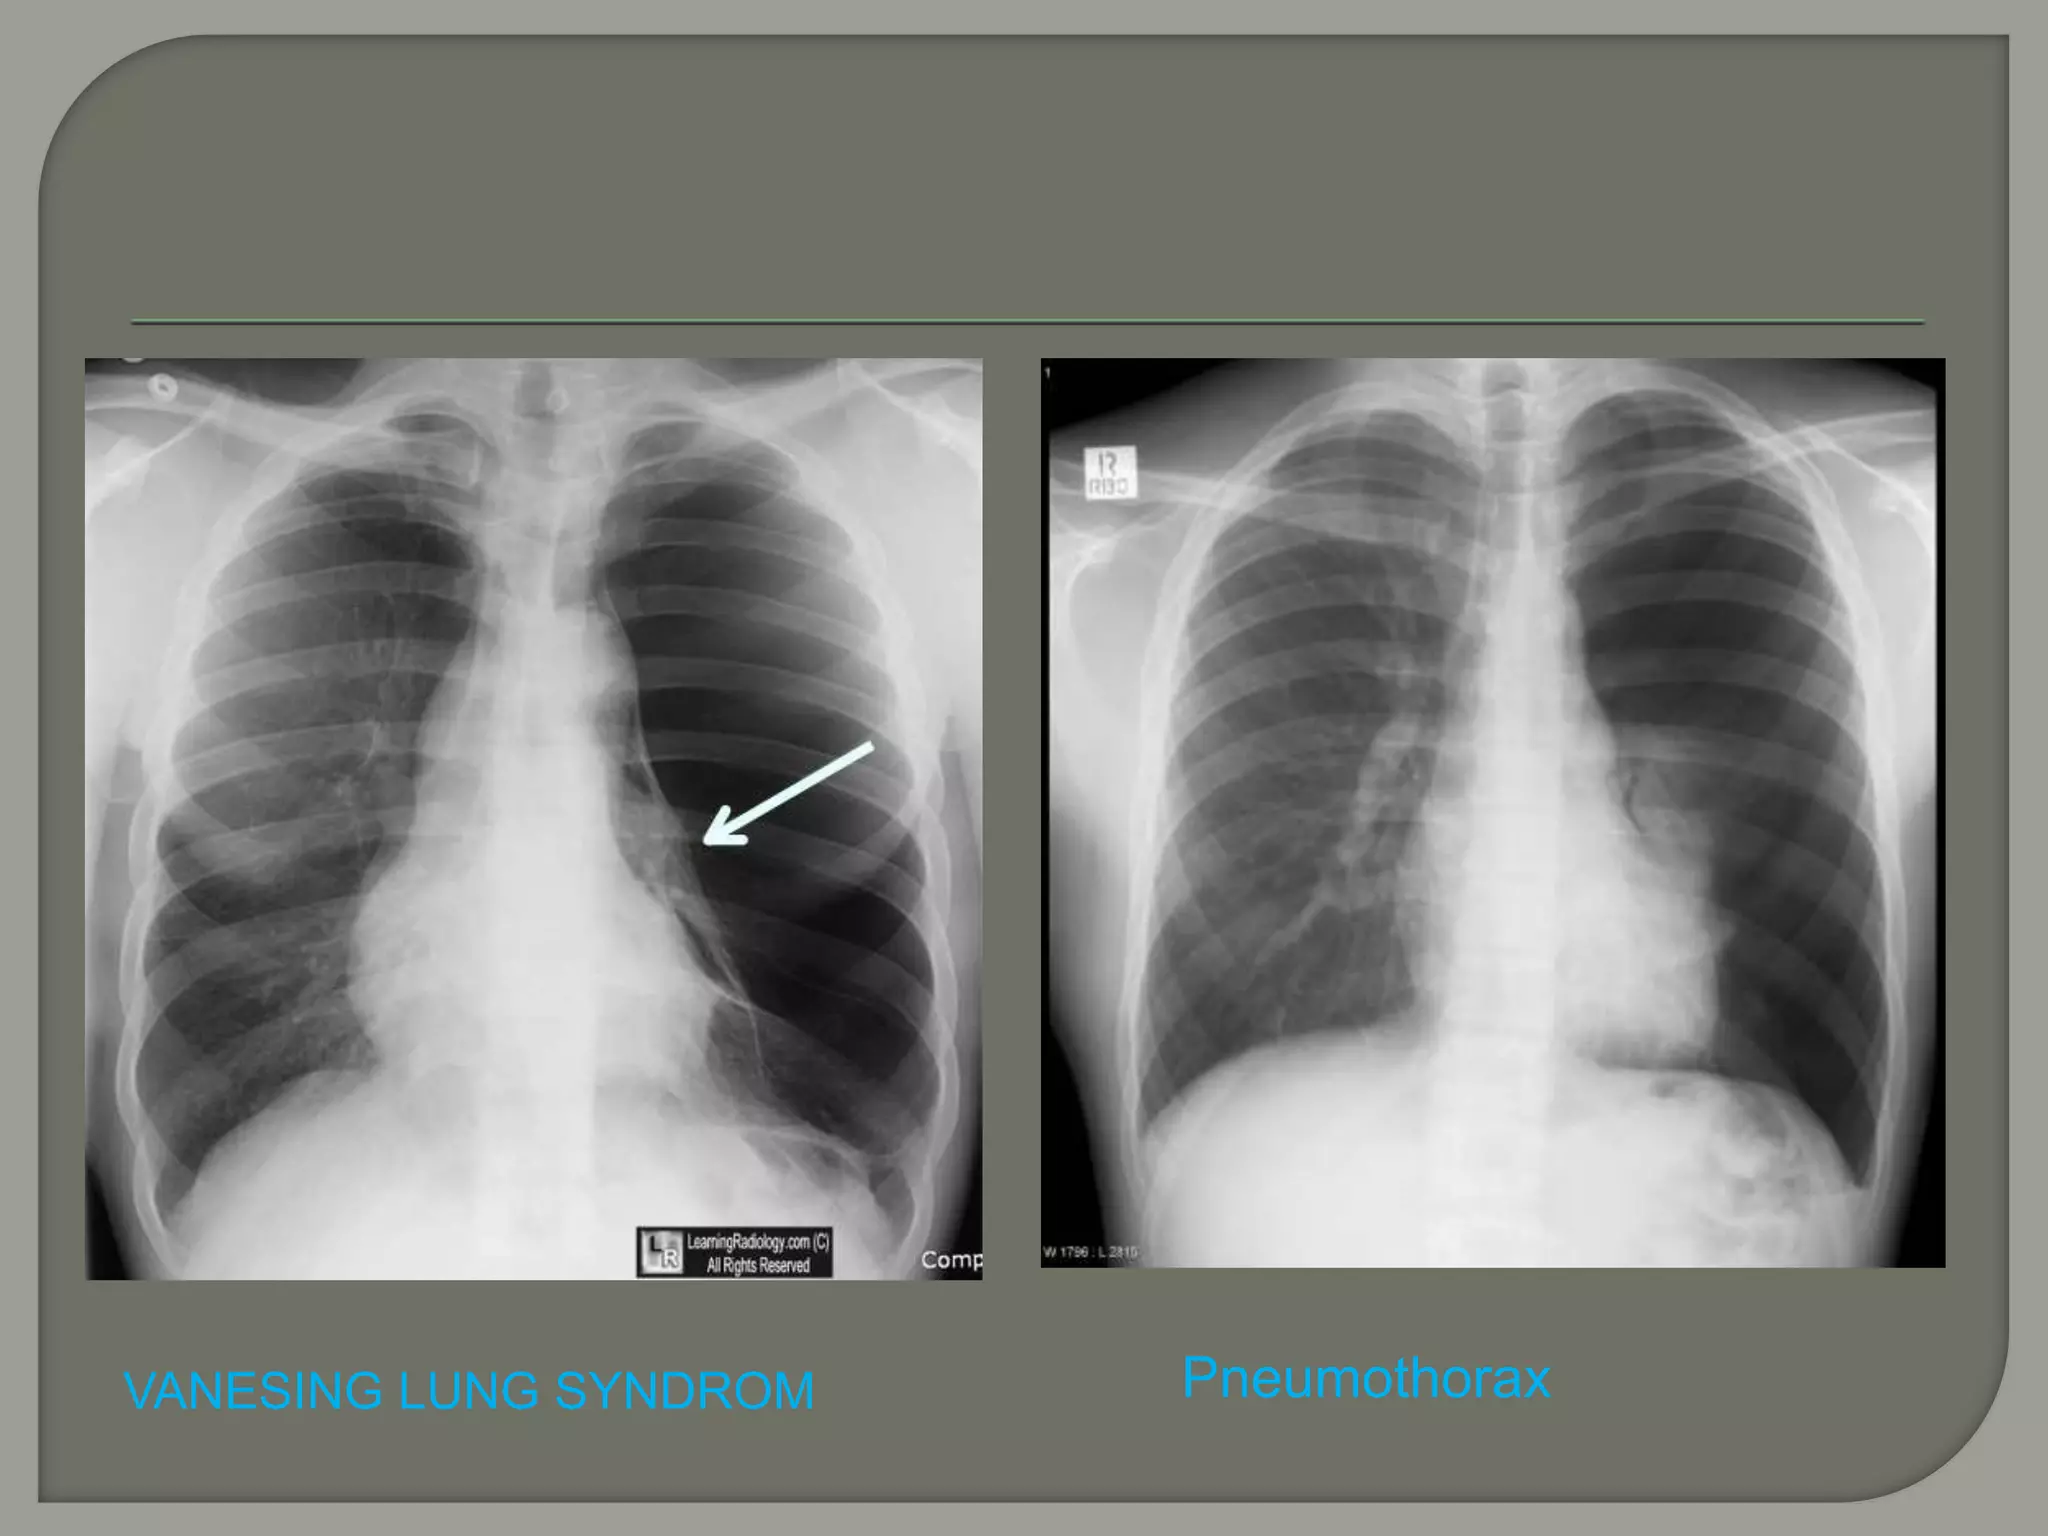

VANESING LUNG

SYNDROM

VANESING LUNG SYNDROM Pneumothorax

 Commonly occurs with small bulla affecting lung apices

 May be difficult to differentiate large bulla from

pneumothorax

 Edge of a pneumothorax will usually parallel the chest wall

curvature whereas edge of a bulla frequently curves

inwards away from the chest wall

 In general, the pleural line associated with a large bulla is

usually concave relative to the lateral chest wall, whereas

the pleural line associated with a pneumothorax is convex

relative to the lateral chest wall. Similarly observation of “the

double-wall sign” (i.e., the presence of air on both sides of

the bulla wall) may be helpful in identifying the findings as

due to a bulla.

 CT may help